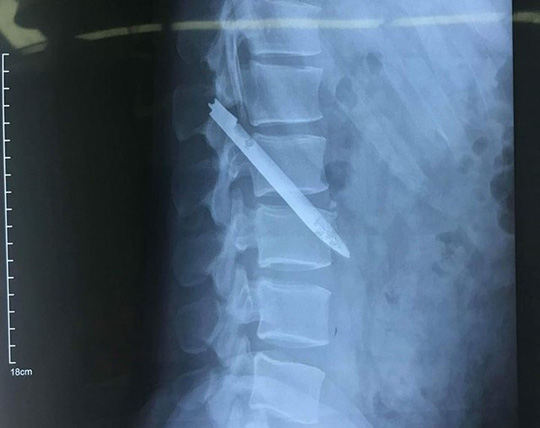

Bệnh nhân nhập viện là một chiến sĩ công an và có triệu chứng đau ở lưng. Ngay sau khi được các bác sĩ khám, chụp chiếu X-Quang thì đã bất ngờ phát hiện có một lưỡi dao dài 13 cm nằm ở vùng cột sống thắt lưng trong suốt 11 năm.

Bệnh nhân Nguyễn Bá Trường Nam sinh ngày 1984 hiện đang là một chiến sĩ công an thuộc đơn vị Công an tỉnh Nghệ An đã nhập viện khi có triệu chứng đau lưng. Anh Nam cảm thấy bị đau lưng dữ dội nên đã quyết định tới Bệnh viện đa khoa tỉnh Nghệ An để kiểm tra. Tại đây các y bác sĩ đã khám và cho anh chụp X-Quang và đã phát hiện ra một lưỡi dao dài 13 cm ở thắt lưng. Ngay sau đó anh được các bác sĩ tại khoa quyết định mổ để lấy lưỡi dao ra. Sau 5 ngày được phẫu thuật lấy lưỡi dao ra khỏi cơ thể, sức khỏe bệnh nhân Nam đã dần dần phục hồi.

Đựợc biết thì vào đầu tháng 4 vừa qua, trong lúc đá bóng anh Nam đã cảm thấy đau lung dữ dội nên đến bệnh viện Hữu nghị đa khoa tỉnh Nghệ An để kiểm tra. Khi khám và chụp X-Quang đã phát hiện có dị vật bằng kim loại nằm gần vùng cột sống thắt lưng của anh. Khi được biết dị vật nằm trong cơ thể anh dài 13 cm anh đã khá bất ngờ về thông báo này của bác sĩ. Nhưng khi anh chấn tĩnh lại và nhớ về khoảng thời gian trước khi anh phải đi công tác tại huyện Thanh Chương tỉnh Nghệ An năm 2007. Anh Nam trong một lần truy bắt đối tượng truy nã anh đã bị đối tượng đâm nhiều nhát vào đầu, lưng dẫn đên chảy máu nhiều và phải nhập viện cấp cứu. Sau khi điều trị tại bệnh viện khoảng 1 tháng anh đã được xuất viện. Anh Nam cho biết, sau khi bị thương thỉnh thoảng anh vẫn thấy hiện tượng đau ở vùng lưng nhưng không đi khám kiểm tra.

Chỉ đến khi cơn đau dữ dội quá không chịu được anh mới đi khám ở ngày 17/4 thì các bác sĩ phẫu thuật thần kinh cột sống thuộc bệnh viện hữu nghị đa khoa Nghệ An đã phát ra và đã lấy dị vật ra. Dị vật dài 13 cm là một lưỡi dao nawngm chéo vùng cột sống thắt lung của bệnh nhân Nam, hiện tại dị vật đã bị gỉ và nằm ở vị trí nguy hiểm, sát động mạch chủ bụng nên nếu trường hợp bệnh nhân vận động mạch sẽ có thể khiến lưỡi dao di chuyển gây tổn thương mạch máu và ảnh hưởng đến tính mạng của anh Nam.